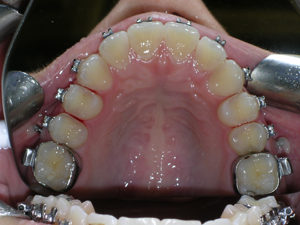

Here’s a case of crowding treated by trimming or narrowing of teeth. Also we utilized temporary anchor devices (mini screws) to help us keep the front teeth from sticking out too much.

Take a look at the braces applied as well as the trimming we did. Elastics were used from the mini screws.